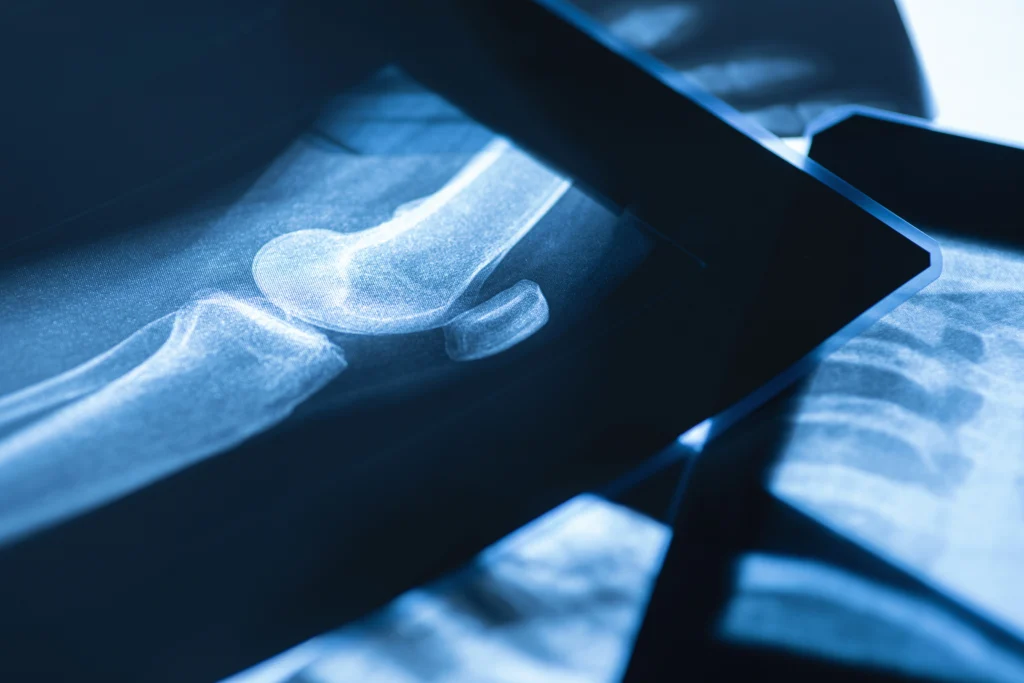

Az ízület felépítése és regenerációs lehetőségei terapia24 1

Az ízület felépítése és regenerációs lehetőségei terapia24 4

Az ízület felépítése és regenerációs lehetőségei terapia24 3

Az ízület felépítése és regenerációs lehetőségei terapia24 2